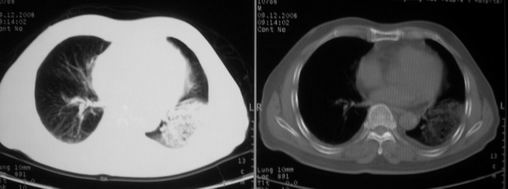

ct左肺下叶大片状高密度影,病变密度不均,界限不清,左侧胸腔积液,治疗后复查临床症状好转而影像学表现病变有发展,还是首先考虑感染性病变,复查时间短附合感染性病变的病理改变。

两肺炎症感染(以左肺下叶为著),双侧少量胸腔积液;建议继续抗炎治疗。